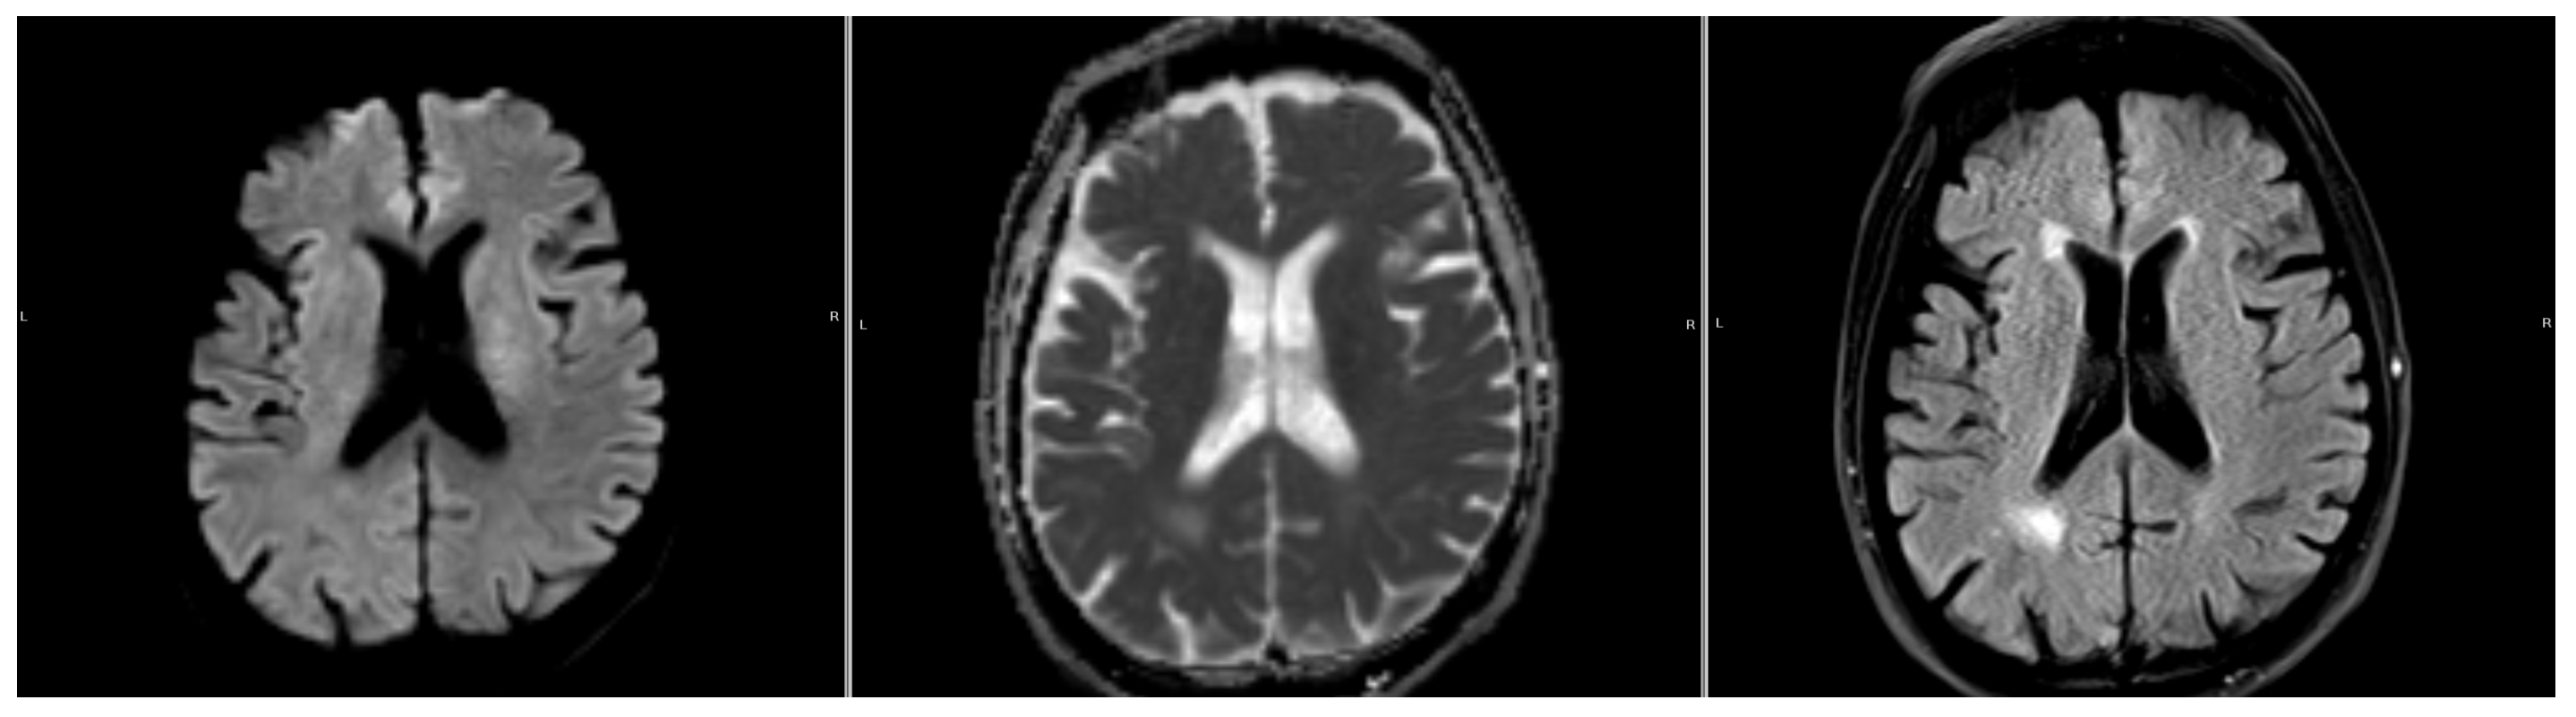

Figure 2. A sample where the automatic DWI segmentation has missed the stroke, located next to the ventricle. From left to right: DWI (b1000), ADC, and FLAIR.